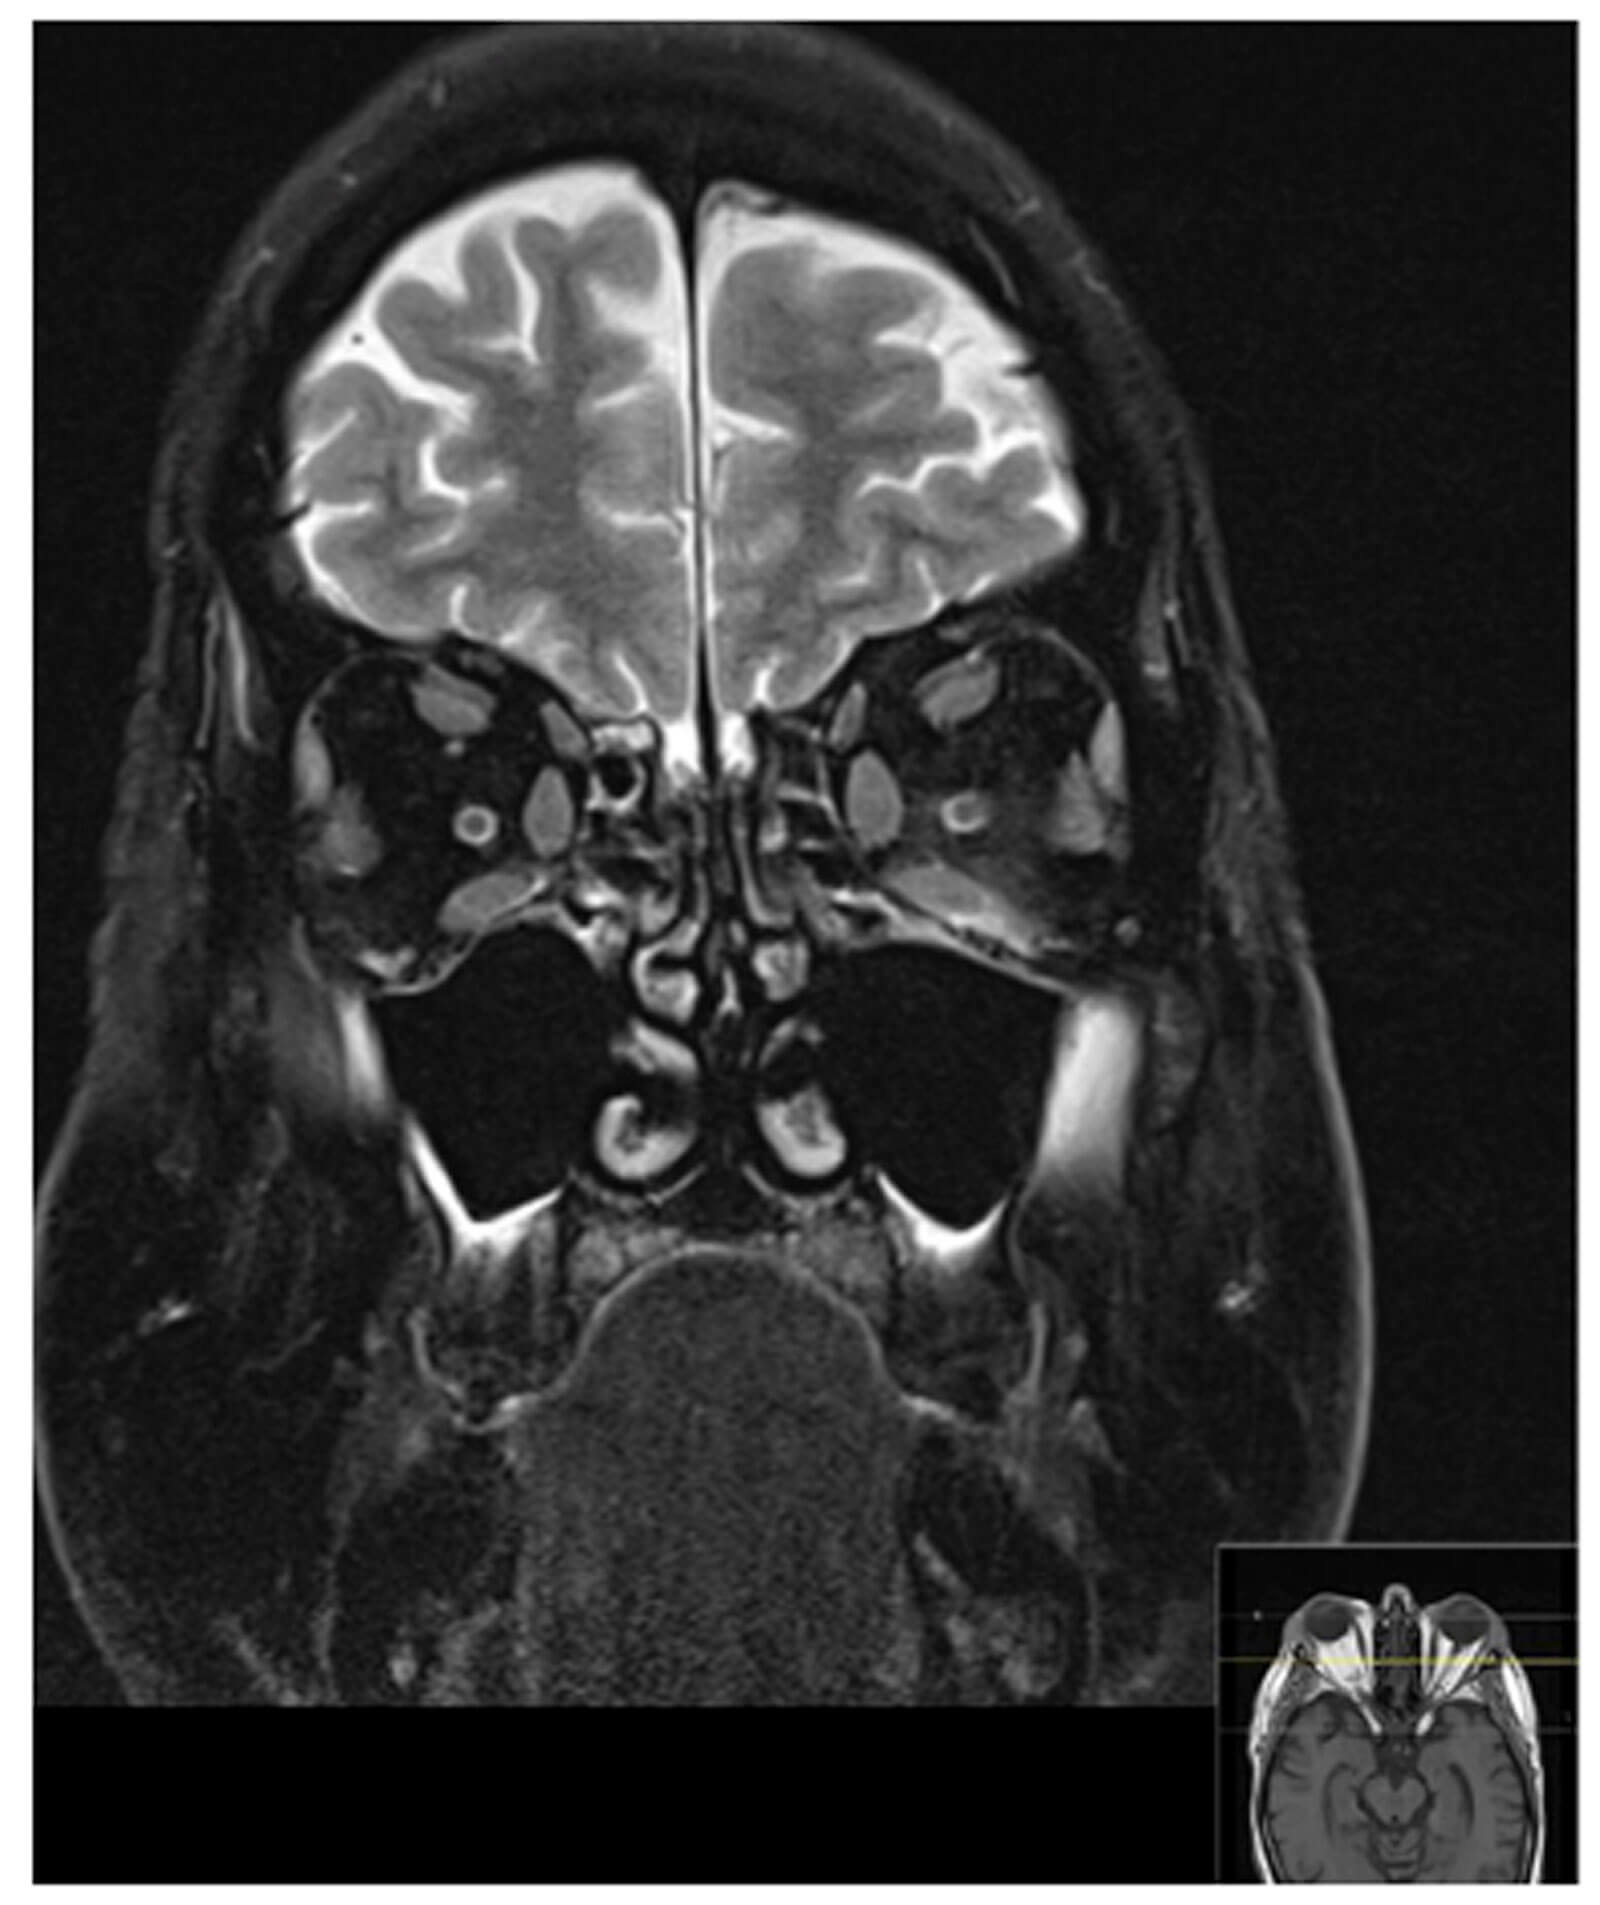

Imaging studies of the orbit such as ultrasound, computed tomography (CT) and magnetic resonance imaging (MRI) can help confirm TED whilst excluding other differential diagnoses. CT without contrast is most popular as it shows bony anatomy of the orbit and is more cost effective compared to MRI. CT orbits can show you characteristic TED changes such as enlargement of the extraocular muscle bellies and sparing of the tendons. Typically, there is asymmetrical bilateral involvement of the extraocular muscles affected in the following pattern: inferior recti, medial recti, superior recti, lateral recti and the obliques. If compressive optic neuropathy from orbital apex crowding is suspected, MRI is the gold standard imaging choice [14].

Figure 2: MRI orbit showing mild bilateral proptosis and conal fat hypertrophy. There is there is small volume fluid around the left inferior rectus muscle and inflammatory change within the adjacent intra- and extraconal fat. There is also small volume fluid around the right inferior rectus muscle and minor inflammatory change to a lesser degree. All four ocular muscle bellies are symmetrically slightly enlarged but return normal signal. No discrete collections are seen.